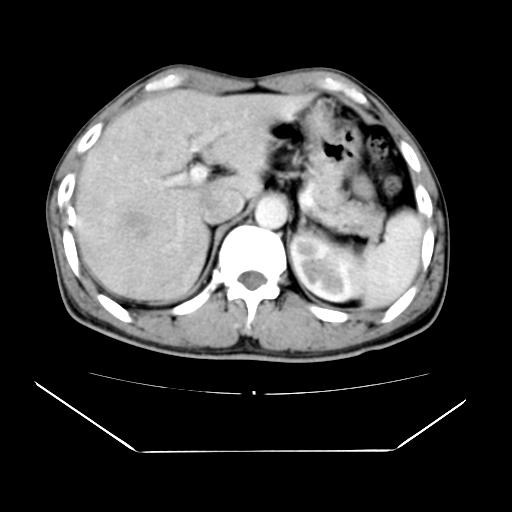

男性,55岁,外院体检afp明显升高,但b超未发现异常,否认乙肝病史。来我院ct增强。有延时扫描。

延时扫描完全充填,血管瘤

肝脏右叶动脉期可见低密度影,至延迟期被充填,考虑血管瘤可能性大。

不排除肝右叶肝癌可能。

如果这个是癌灶的话则下腔静脉有瘤栓可能

肝6段血管瘤

血管瘤可能性大。

考虑肝右静脉影。